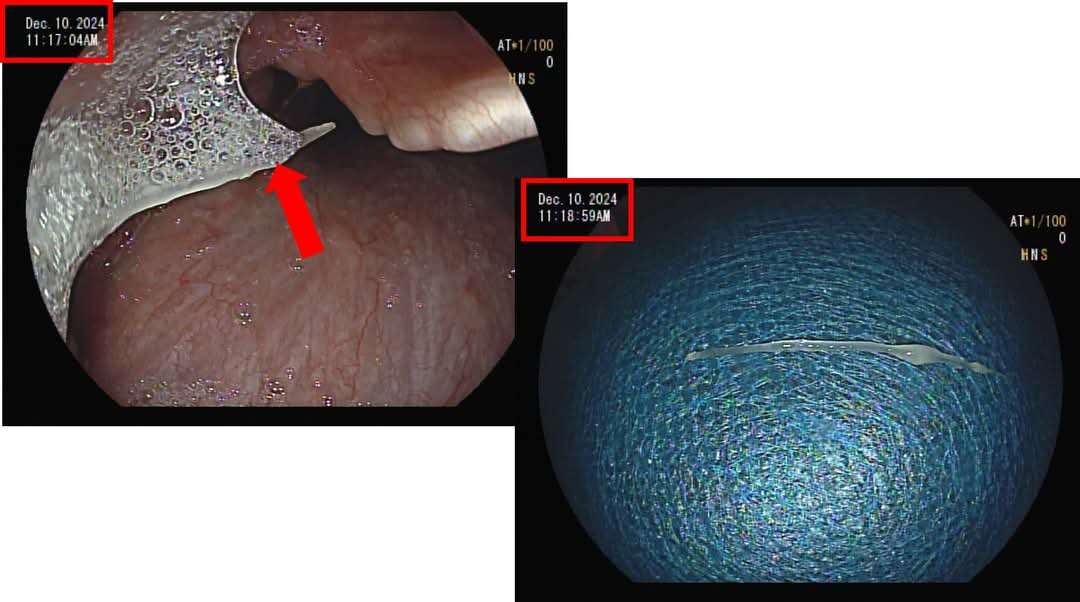

根據《都市頻道》報導,河南省一名29歲男子吃紅燒魚突然被魚刺卡住喉嚨,想說趕快喝醋、吞幾口飯想把魚刺壓下去。可是到了第二天,男子仍吞嚥不適,還出現吐血症狀。送醫檢查才驚覺,那根5公分長的魚刺已經刺穿食道和主動脈,開刀後仍回天乏術。

方冠傑醫師建議,盡早尋求耳鼻喉科或是腸胃科醫師協助將異物取出,「若尖銳異物刺入太久,有機會造成深部感染穿孔,嚴重時甚至會危及生命。」